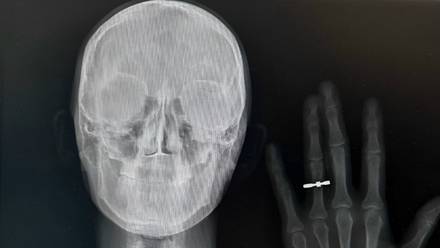

Рентгеновский снимок молодоженов из Новосибирска Кристины Шрайнер и Станислава Ефремова

Рентгеновский снимок молодоженов из Новосибирска Кристины Шрайнер и Станислава Ефремова / Фото: Предоставила Кристина Шрайнер

Предложение руки и сердца и свадьба — пожалуй, самые важные моменты в жизни каждой пары. Можно ли сделать их еще более запоминающимися? Пара медиков запустила новый тренд: они сделали рентген с обручальными кольцами. Об этой и других необычных свадебных задумках узнала «Вечерняя Москва».

Фото — рентгеновский снимок с рукой и кольцом на безымянном пальце — быстро разлетелось по сети. Оказалось, что так медики решили сообщить своим друзьям о предстоящей помолвке.

Кстати, первым подобный снимок сделал немецкий ученый Вильгельм Конрад Рентген, открывший рентгеновское излучение.

В 1895 году в ходе эксперимента он запечатлел руку его жены Анны Берты Людвиг с кольцом. Этот кадр стал первым рентгеновским снимком в истории.

В 2023 году такую задумку решилась повторить пара врачей из Владивостока. А недавно подобный снимок сделали и другие молодожены, также преданные медицине, но уже из Новосибирска. Как раз они и прославились в сети.

— Мы оба врачи. Я работаю эндоскопистом, а мой жених Станислав — рентгенологом. Предложение он мне сделал в домашней обстановке. Сообщить родным, которые долго ждали этого события, хотелось красиво. Эта идея показалась нам очень символичной, — рассказывает невеста Кристина Шрайнер.